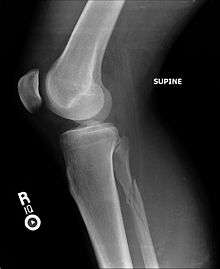

Upper fibula fracture